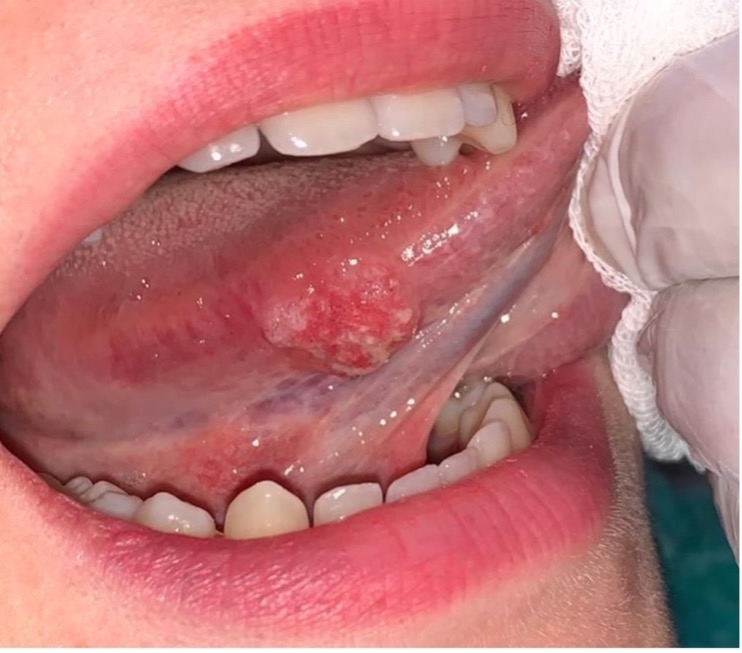

Ca-Cheek/ longue (RND)

At Indotaj Medical Center, our priority is to offer personalized and compassionate care for individuals with oral cavity cancers, ensuring a comprehensive and supportive approach throughout the treatment journey If you are referring to cancer in the cheek (Ca-Cheek) or tongue (Ca-Tongue) and the mention of “RND” stands for Radical Neck Dissection, it implies a surgical procedure often done in the management of head and neck cancers, including those affecting the cheek and tongue. We provide the best treatment at Indotaj Medical Center for Ca-Cheek/ longue (RND) diseases.